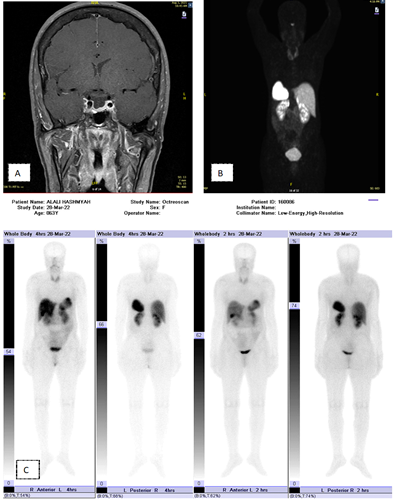

A pituitary MRI revealed a partially empty sella, with no evidence of pituitary adenoma (Figure 1) In order to exclude an ectopic source of the GH hypersecretion, further imaging (CT CAP, octreotide scan) tests were performed, all were normal. Whole-body 68 Gallium DOTATATE PET/CT revealed normal uptake in the pituitary and body (Figure 1). Thyroid US showed, two nodules the left lobe, measuring 2 cm (TR3 & TR4) with benign cytology. She refused to do colonoscopy.  As clinical context of acromegaly with an empty sella, patient has been commenced on 20 mg monthly octreotide acetate. After receiving 4 doses of octreotide, her IGF-1 & GH has reduced (Table 1,2) (Figure-1).

Figure 1 A: MRI shows empty Sella, B: DOTATATE PET/CT showing receptor activity in the pituitary gland due to physiological somatostatin receptor expression & C: Octreotide scan shows physiological radiotracer distribution with no abnormal activity to suggest neuroendocrine tumor.